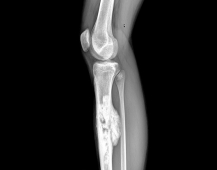

El osteosarcoma es el tipo de sarcoma óseo más común y suele aparecer entre los 15 y 30 años. Aunque es una enfermedad poco frecuente —con una incidencia de aproximadamente 1 caso por millónde personas al año— su comportamiento agresivo hace que el diagnóstico precoz y el tratamiento oportuno sean claves para mejorar el pronóstico.

“El osteosarcoma es un cáncer que se origina en las células que forman el hueso. Afecta principalmente a adolescentes y adultos jóvenes, y su tratamiento debe ser rápido y coordinado para lograr los mejores resultados”, explica el Dr. Orlando Wevar, jefe del equipo de Oncología Ortopédica del Instituto Traumatológico.

El tratamiento del osteosarcoma combina quimioterapia, cirugía y en algunos casos radioterapia. Gracias al GES, el diagnóstico, tratamiento y seguimiento están garantizados, lo que permite un acceso más equitativo y oportuno para pacientes de todo el país.